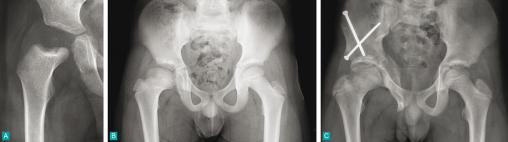

C. Réalisation d'une ostéotomie du bassin de couverture à type de triple ostéotomie pelvienne.

Résultat à l'âge de 13 ans montrant une bonne couverture de la tête fémorale avec une tête sphérique.